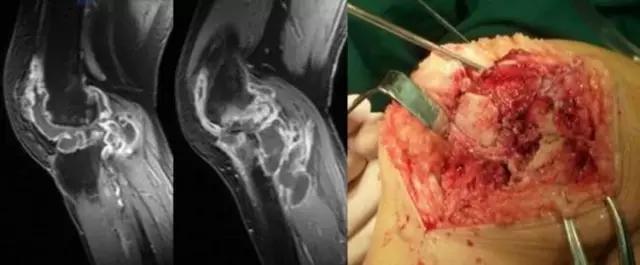

膝关节结核为侵袭性病变,会破坏膝关节的滑膜、软骨、骨等,所形成的寒性脓疡会顺着组织间隙流注,与其他疾病的表现不同。 病例:李XX,女,56岁,右膝关节疼痛逐渐加重8个月。手术及病理证实为膝关节结核。

利用临床检查——

临床检查更应该是临床医生的长处,密切结合临床检查阅片时才能有的放矢。 病例:吴XX,女,24岁,右膝关节内侧疼痛不能触摸5年。曾在多家医院局部封闭等治疗。查体:右膝关节外观无明显变化,屈伸好,膝关节前内下方有固定的压痛点,不给用力压迫。 MRI:膝关节内无明显改变,临床检查压痛部位有小范围高信号,中央有混杂信号。(诊断报告正常) 考虑:膝关节血管瘤。

该患者手术时肉眼所见及术后病理确诊为血管瘤。